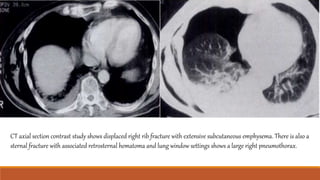

CT axial section contrast study shows displaced right rib fracture with extensive subcutaneous emphysema. There is also a

sternal fracture with associated retrosternal hematoma and lung window settings shows a large right pneumothorax.